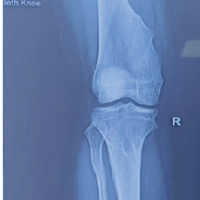

A 32-year-old male presented with pain in the left knee with stiffness for 1 year following a history of twisting injury to the knee while walking. He gave a history of locking episodes and difficulty in squatting and sitting cross-legged. He was a known case of chronic gout for 3 years on irregular medication. His father was a known case of Gout and was on treatment for 25 years. On examination, the patient had ichthyosis over both legs since childhood and mild effusion over the knee, with lateral joint line tenderness and a flexion deformity of 20°. The knee was stable without laxity, with a range of motion (ROM) from 20° to 70°, which was painful. (Fig. 1).

He had no other palpable gouty lesion in the body. He had an elevated serum uric acid of 13.4, with other normal blood parameters. The patient had a pre-operative Lysholm knee score of 35/100. MRI revealed Arthrofibrosis with lateral meniscal tear with mucoid degeneration of anterior cruciate ligament (ACL) with synovitis. The report did not mention any evidence of chondrocalcinosis. Due to the patient’s chronicity of mechanical symptoms and meniscal tear, the patient was taken up for diagnostic arthroscopy. The arthroscopic examination revealed synovitis with widespread chalky deposits over the chondral surfaces, menisci, fat pad, ACL and synovium in the suprapatellar pouch and intra-articularly. (Fig. 2).